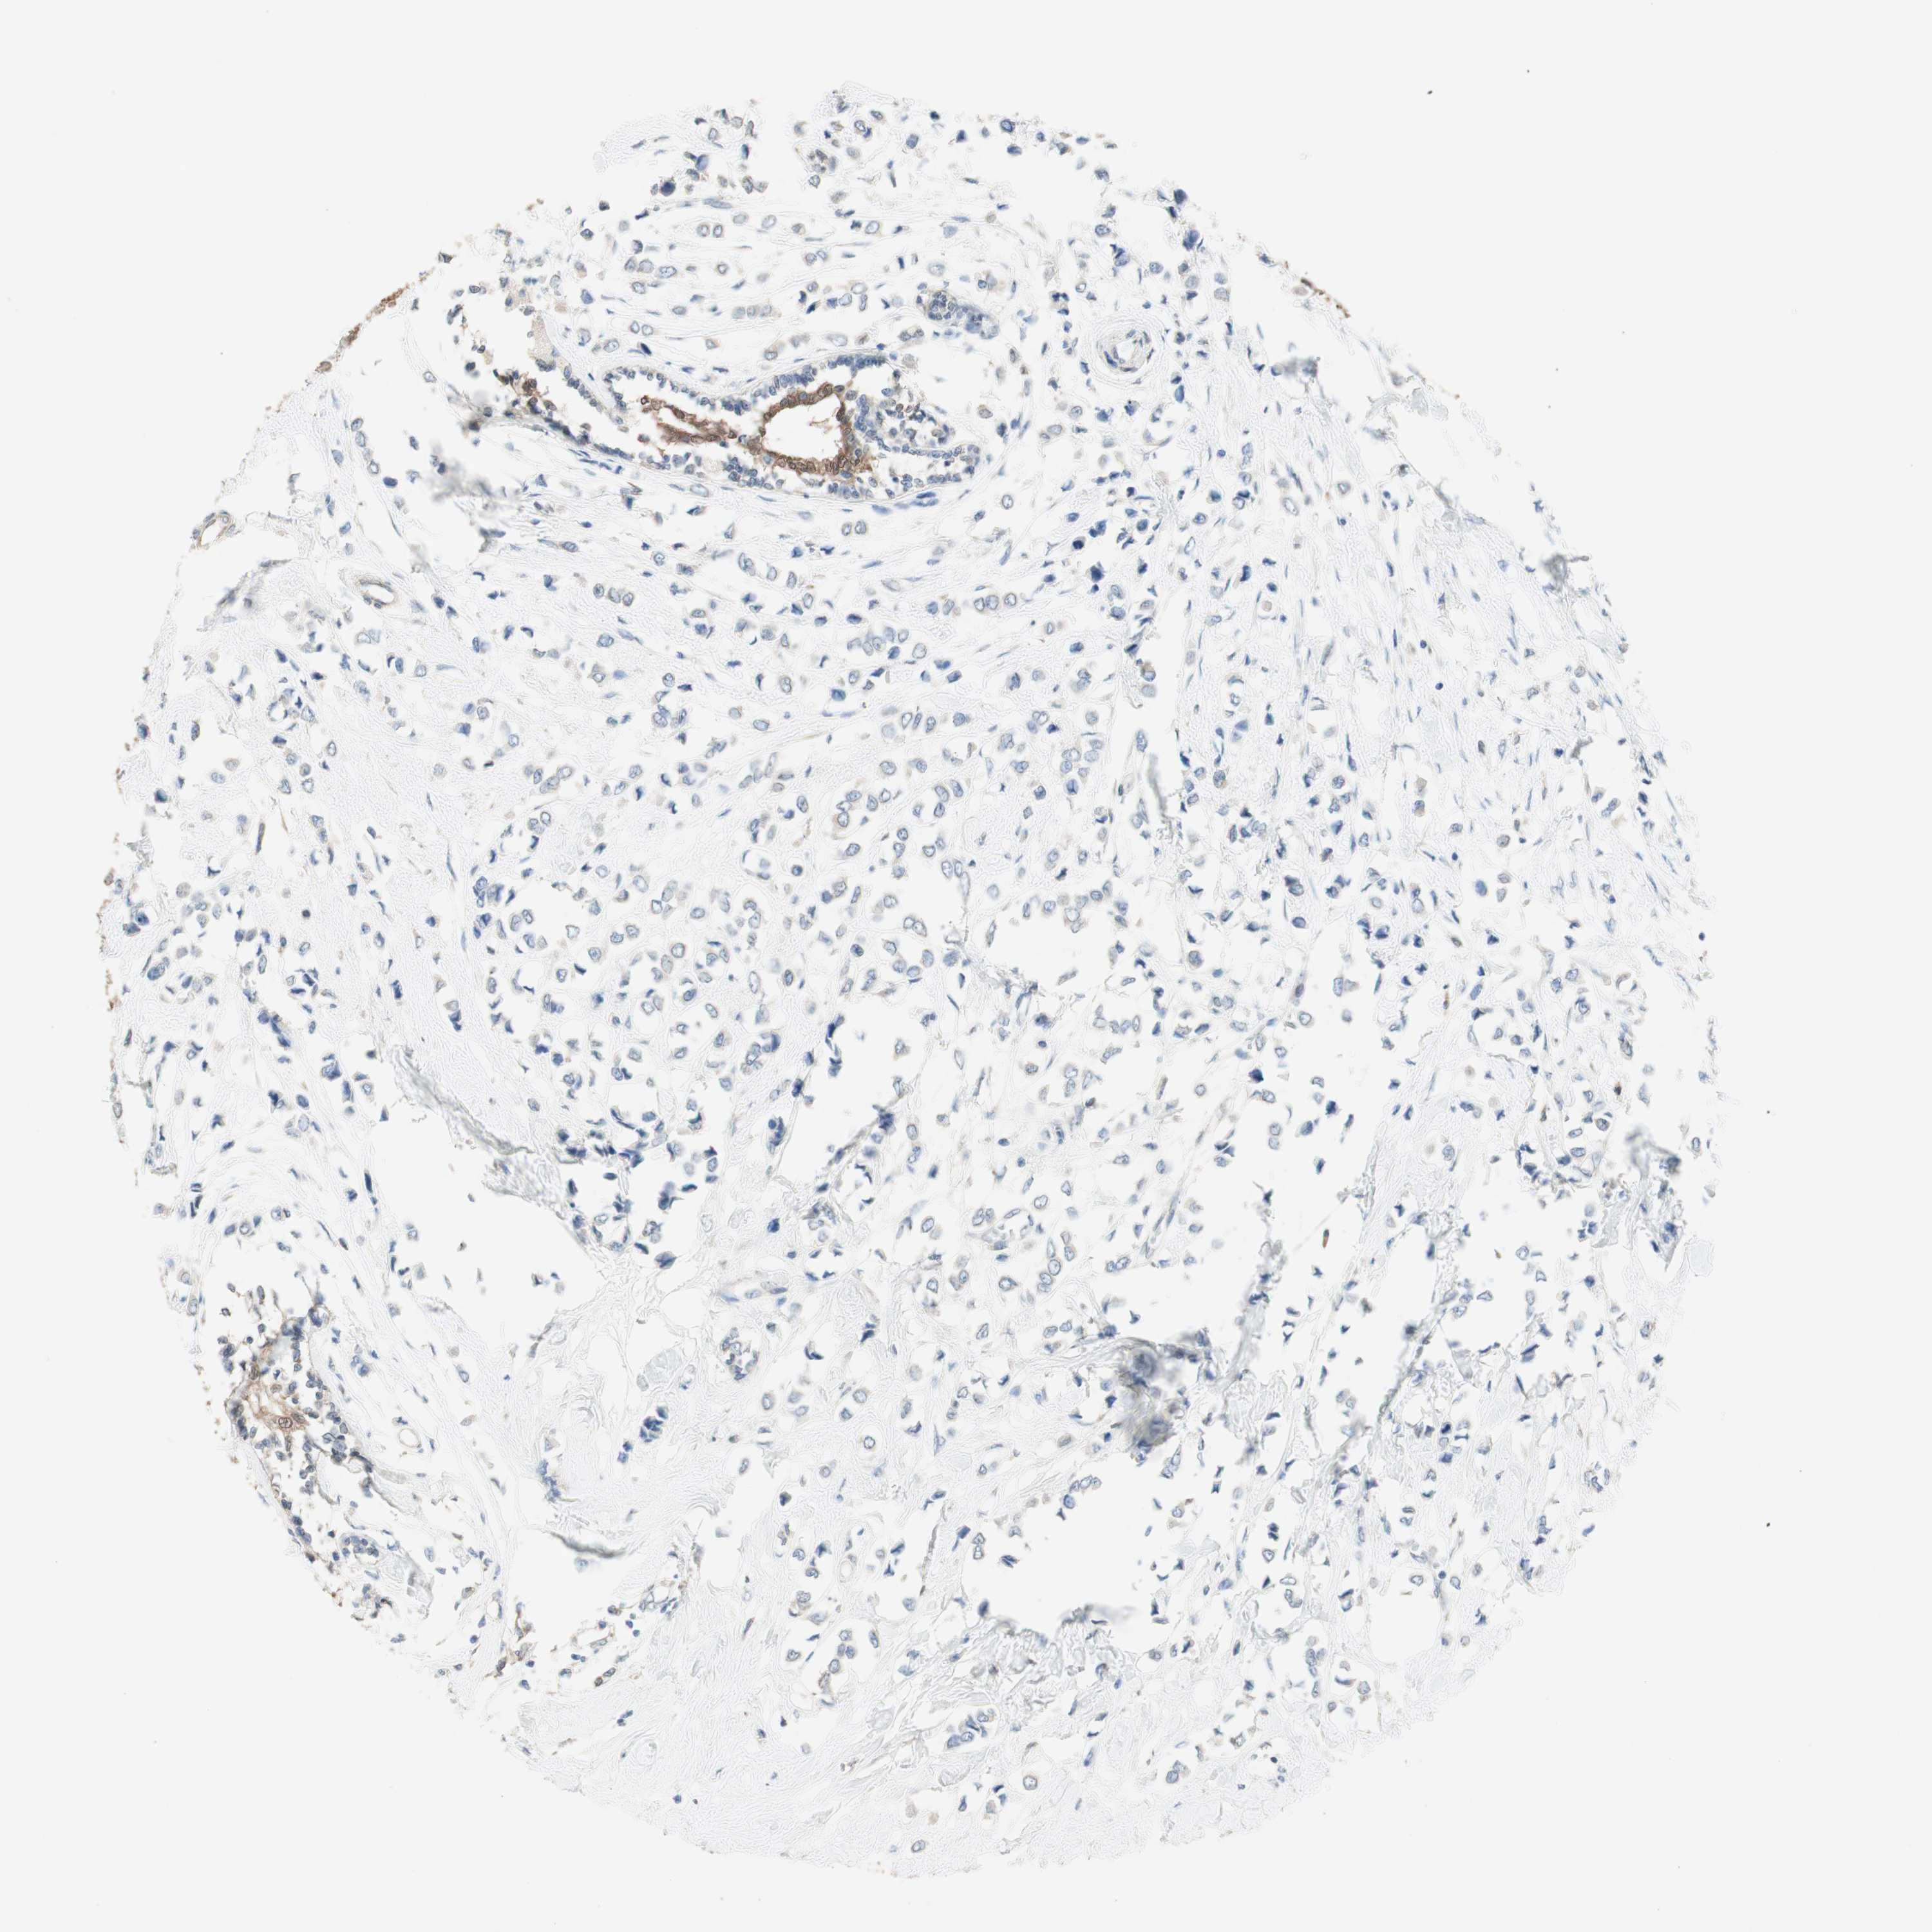

CANCER BREAST CANCER Show tissue menu

BRCA TCGA BRCA VALIDATION PROTEIN EXPRESSION

ANTIBODIES

AND

VALIDATION